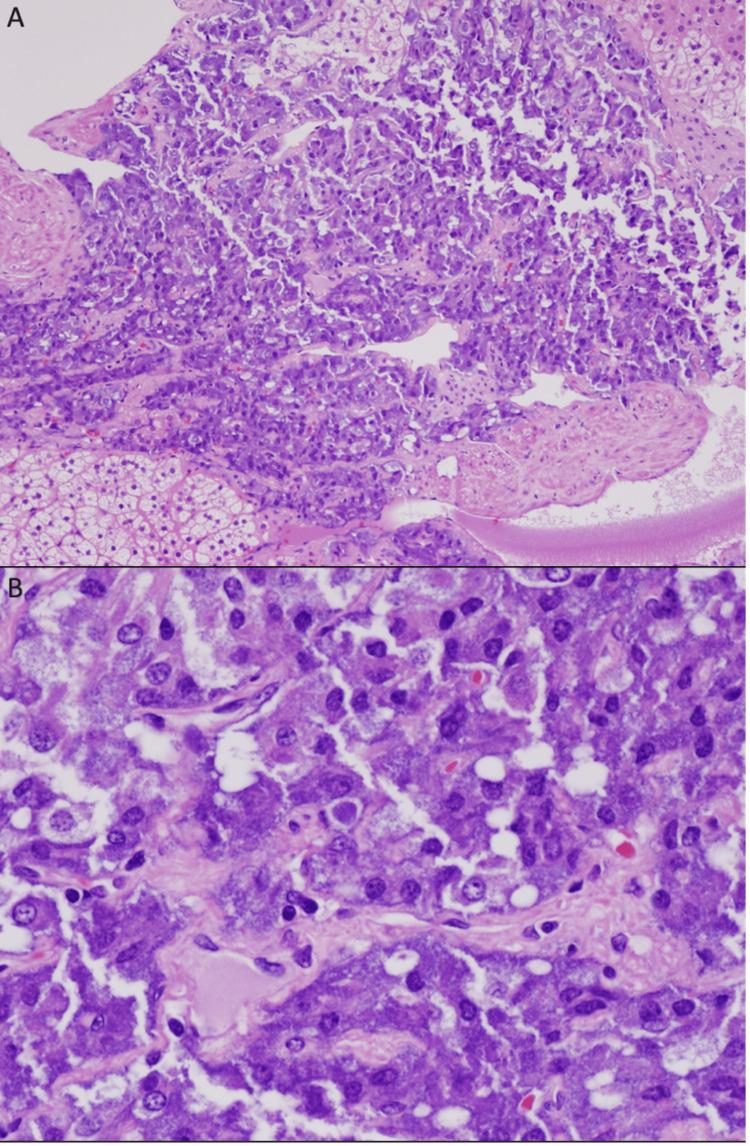

Paragangliomas are catecholamine-secreting neuroendocrine tumors that originate from the chromaffin cells of the sympathetic ganglia. Roughly 10% of paragangliomas are malignant, resulting in a rare occurrence of 90-95 cases per 400 million people. Herein, we report a case of a 29-year-old female patient who presented with nausea, vomiting, and bloating and was found to have a large left retroperitoneal tumor upon imaging. The tumor was successfully removed, and subsequent histological analysis was compatible with the presence of a paraganglioma. This case serves as a reminder that despite its rarity, paragangliomas should never be dismissed as a differential diagnosis if correlating symptoms and diagnostic findings are consistent with that of paraganglioma etiology.

副神经节瘤是一种分泌儿茶酚胺的神经内分泌肿瘤,起源于交感神经节的嗜铬细胞。大约10%的副神经节瘤是恶性的,每4亿人中仅有90 - 95例的罕见发病率。在此,我们报告一例29岁女性患者,该患者出现恶心、呕吐和腹胀症状,影像学检查发现左腹膜后有一个大肿瘤。肿瘤被成功切除,随后的组织学分析结果与副神经节瘤相符。该病例提醒我们,尽管副神经节瘤罕见,但如果相关症状和诊断结果与副神经节瘤病因一致,就绝不能排除其作为鉴别诊断的可能性。